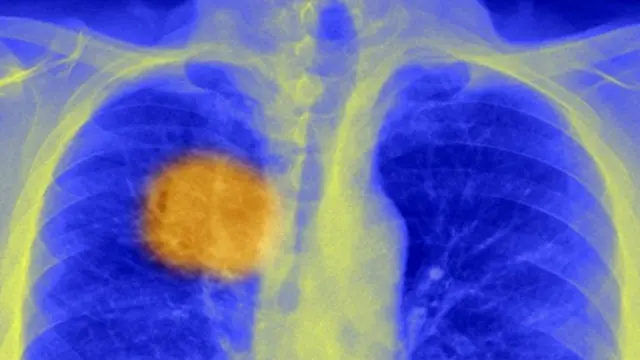

Ученые обещают, что скоро рак будут лечить одним уколом

Британские ученые утверждают, что нашли способ заставить иммунную систему человека эффективно бороться с раковыми опухолями.

Его суть заключается в том, чтобы найти самое уязвимое место каждой отдельно взятой опухоли – так сказать, ее Ахиллесову пяту – и нацелить на него иммунную систему.